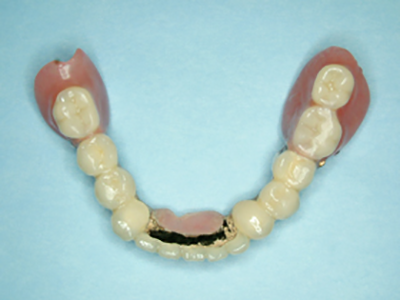

ふくしま歯科医院では、患者様の生活の質を高める多彩な義歯治療を提供しています。特にコーヌスクローネ義歯は同院が豊富な症例実績を持つ専門分野です。

コーヌスクローネ義歯は、残存歯に金属冠を装着し、その上から入れ歯を被せる革新的な設計です。茶筒のふたのような構造により、従来の金具(クラスプ)で固定する方式と異なり、歯に横方向の無理な力がかかりにくくなっています。これにより残存歯への負担を軽減しながら、義歯の安定性を大幅に向上させることが可能です。また、装着時に金具が一切見えないため、周囲の方に入れ歯と気づかれにくいという審美的メリットも備えています。実際の症例では、歯周病で弱った歯も義歯と一体化して固定され、咬合力が歯の軸方向に適切に分散。ぐらつきが解消され、硬い食物もしっかり噛めるようになりました。